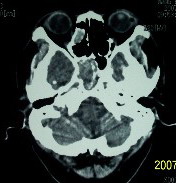

f    29岁   头闷  头晕1月余

肿瘤累及颅底前颅窝,部分层面见散在钙化,中心坏死。支持:脑膜瘤!

右额叶底部巨大等低混杂密度肿块,边界清楚,周围水肿轻度,明显占位效应。蝶鞍扩大,部分骨质破坏。

考虑脑膜瘤,建议增强扫描进一步检查。

蝶鞍受压吸收,可以排除室管膜瘤。肿瘤最大层面不在蝶鞍可以排除垂体瘤。支持脑膜瘤